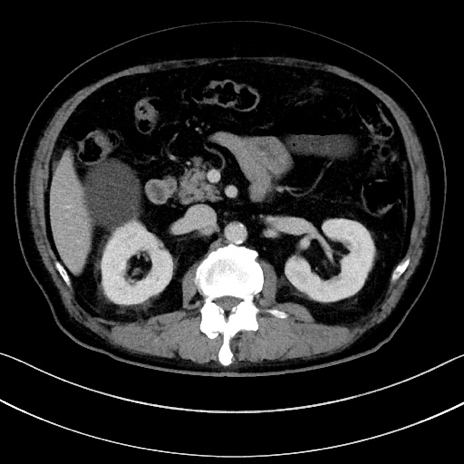

症例15(横断像)

【症例】70歳代男性

【主訴】腹痛

【現病歴】今朝から腹痛あり。全体的に痛い。特に左上の方。排ガスが今日はない。冷や汗が出る。

【既往歴】直腸癌術後

【身体所見】左側腹部〜上腹部に圧痛あり。腹膜刺激症状明らかなではない。軽度反跳痛。左下腹部に術後瘢痕あり。

【データ】WBC 7700、CRP 0.02